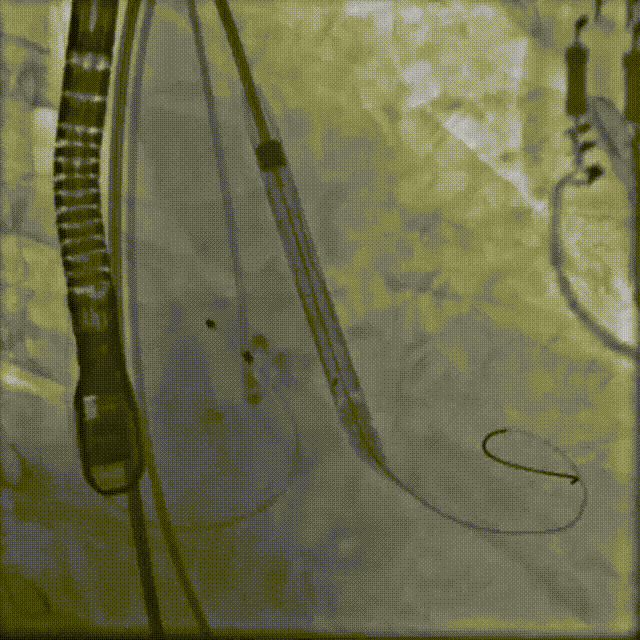

手术过程概览

置入猪尾进行根部造影,造影可见根部钙化不均匀,冠脉灌注良好。

根部造影

20mm球囊预扩,无腰征,冠脉显影良好,无造影剂渗漏。

20mm球囊预扩

TaurusElite AV26瓣膜轻松过弓跨瓣,瓣膜初始定位瓣环0位,120bpm起搏下精准释放,释放到工作位后造影显示锚定充足,位置良好,冠脉未见遮挡,继续完成释放。

瓣膜初始定位

瓣膜释放过程

瓣膜释放后造影观察,根据影像判断反流较多,选择23mm球囊进行后扩。球囊后扩后反流量减少,瓣膜形态佳。

瓣膜脱钩

工球囊后扩

释放后多体位观察造影,提示瓣膜位置良好,展开良好,双侧冠脉未见遮挡,微量瓣周漏。

最终造影

术前跨瓣压差62mmHg

术后跨瓣压差4mmHg